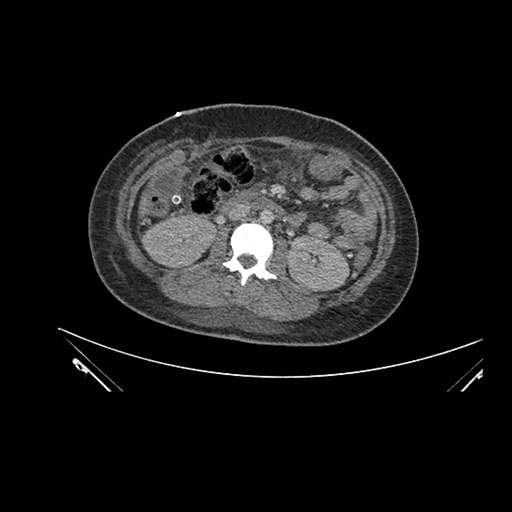

Imaging Analysis

Look through the patient's CT scan to identify any areas of concern for the necessary procedure.

Axial Venous

Based on initial findings, which issue(s) would you be most concerned about?